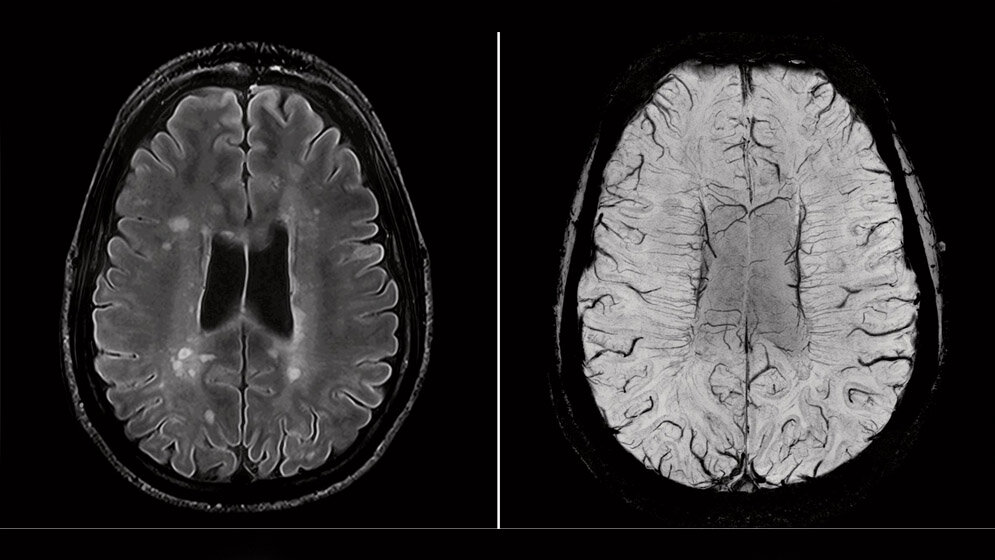

In der klinischen Routine werden zumeist MRT-Scanner eingesetzt, die mit bis zu drei Tesla betrieben werden. Höhere Feldstärken – Fachleute sprechen von „Ultrahochfeld-MRT“ – sind bislang noch vorwiegend der Forschung vorbehalten. Das aktuelle Projekt mit dem Namen „SCAIFIELD“ widmet sich der 7-Tesla-MRT. Europaweit gibt es etwa 20 dieser Geräte, so auch am DZNE in Bonn. Obwohl die hohe Feldstärke prinzipiell eine besonders hohe räumliche Auflösung ermöglicht – sie hat also das Potenzial, feine Details zu erfassen –, bringt diese Technik auch Herausforderungen mit sich. Denn bei der 7-Tesla-MRT ist die Wellenlänge der Radiowellen im Gewebe physikalisch bedingt kleiner als die Größe des menschlichen Kopfes. „Wir haben Wellenberge und Wellentäler, die sich über das Gehirn verteilen und sich zudem überlagern können. Infolgedessen ist das elektromagnetische Feld nicht überall gleich stark. Das verschlechtert an manchen Stellen das Signal-zu-Rausch-Verhältnis und damit die mögliche Auflösung. Im Zentrum des Gehirns ist die Bildqualität gut und wird nach außen hin schlechter“, sagt Prof. Tony Stöcker, Physiker und MRT-Experte am DZNE in Bonn, der das SCAIFIELD-Konsortium koordiniert. „In gewisser Weise ist es so, als ob man in einem dunklen Raum ein großes Wandgemälde mit einer Taschenlampe beleuchtet. Außerhalb des Lichtflecks bleibt das Bild im Halbdunkel. Details sind dann schwer zu erkennen.“

„Letztlich wollen wir Messgrößen generieren, mit denen sich krankhafte Veränderungen des Gehirns mit Zahlenwerten beziffern lassen. Man spricht hier von quantitativen Biomarkern“, so Stöcker. „Wir streben eine Auflösung von einem halben Millimeter an – und zwar in allen drei Raumrichtungen. Die Gewebevolumina, die wir so abbilden, wären fast zehnmal kleiner, als das, was bei MRT-Bildern des Gehirns derzeit Standard ist. Wir könnten also feinere Details erfassen.“ Dabei geht es nicht nur darum, die Ausdehnung von Hirnstrukturen zu vermessen. Die Forscher wollen auch Eigenschaften des Gewebes präzise bestimmen – etwa die Transportfähigkeit für Wasser, den Wassergehalt und andere Parameter ¬– sowie den Blutfluss durch feine Gefäße. Alle diese Messgrößen liefern Informationen über den Zustand des Gehirns.